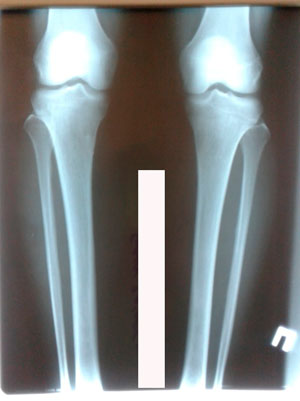

Исходник - 32 года.

Дата операции - 19.03.2020

Дата снятия аппаратов - 26.06.2020